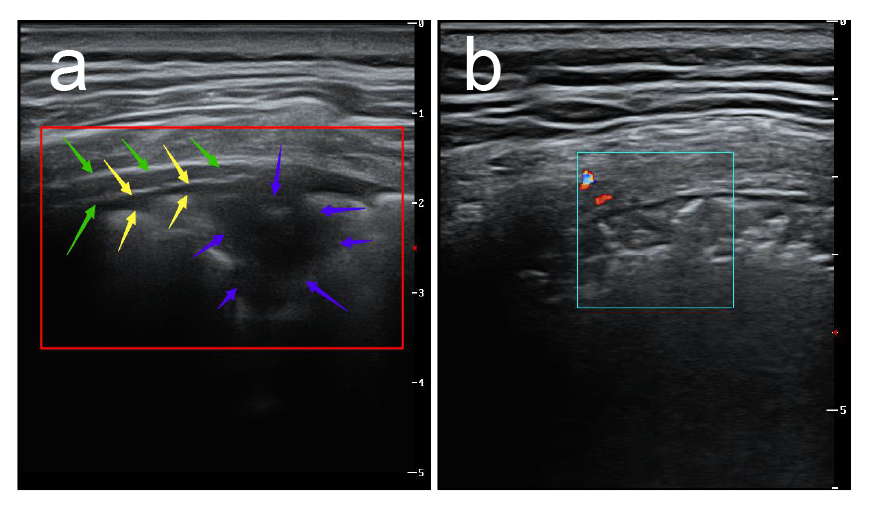

2.超声探查可见胸膜线下多条不连续或连续融合B线(瀑布征),或弥漫性B线(白肺征),同时A线消失。与心源性肺水肿所致B线比较,冠肺B线融合现象更普遍,位置相对也比较固定,B线边缘模糊,无分叉征,起点位于胸膜下病灶较肺水肿B线起点圆钝(凸阵探头)。

3.高频超声显示胸膜线欠光滑、毛糙,连续性中断,主要是由于胸膜下肺泡及间质病变气体含量减少,声波反射减少所致。

4.胸膜下病灶可见多发小斑片样实变,长条样实变。

5.病灶内回声均匀或不均匀,多可见细小支气管肺泡充气征(早期、进展期多见。考虑次级肺小叶受间质炎性侵犯,间质水肿增厚,部分细小支气管及肺泡尚未受侵犯气体含量高所致)或支气管充气征(重症期或局部大片实变多见,考虑原因可能为局部炎症风暴所致大部细小支气管肺泡水肿实变仅留较大支气管或部分肺泡所致伴病灶后弥漫性B线,经观察部分发病时间较长病情趋于好转冠肺患者CT影像呈小结节样实变影,超声亦可见胸膜下结节样不规则回声影,后见融合B线,位置固定。

6.高频超声还可显示病变肺周的胸膜局限性增厚及胸膜下病变周围局限胸腔积液(线阵探头更清晰多数患者胸膜增厚约1-2mm,病灶周胸腔内局限性胸膜下积液约2-3mm)随病情进程有所变化。

7. CDFI超声显示非重症期新型冠状病毒肺炎(COVID-19)患者胸膜下实变病灶血流信号不敏感,随更换多台不同品牌新型超声仪器仍显示呈乏血流表现,具体原因可能与病变的病理性质有关,同时与病变进展时期有关,但应引起高度重视,因普通炎症所致肺实变彩色多普勒超声显示呈丰富血流信号,一般预后较好但新型冠状病毒肺炎(COVID-19)患者病变一般进展迅速,引起患者死亡,是否与肺组织未能迅速建立起丰富微小血管交换机制相关还有待于进一步研究,但值得肯定的是彩色多普勒超声相比其他医疗设备更能有效直观的了解实变肺组织血供信息,对临床医生预先判断患者预后及病情进程有重要的临床价值。